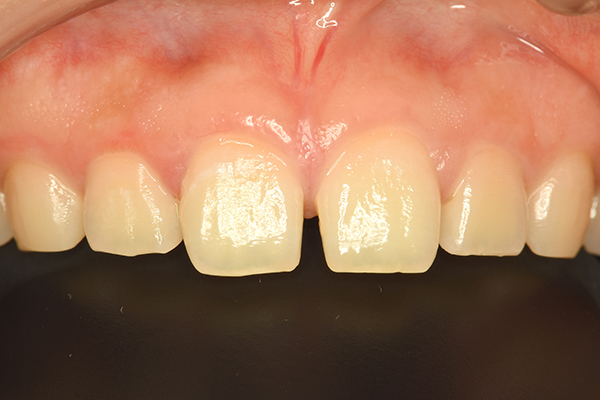

- 上顎3-3の計6本のセラミック矯正

Before

After

| 主訴 | 前歯の凸凹 |

|---|---|

| 治療期間 | 約2ヶ月 |

| 治療費 | ¥1,003,200(税込) |

| 治療のリスク | 処置後の疼痛、違和感 |